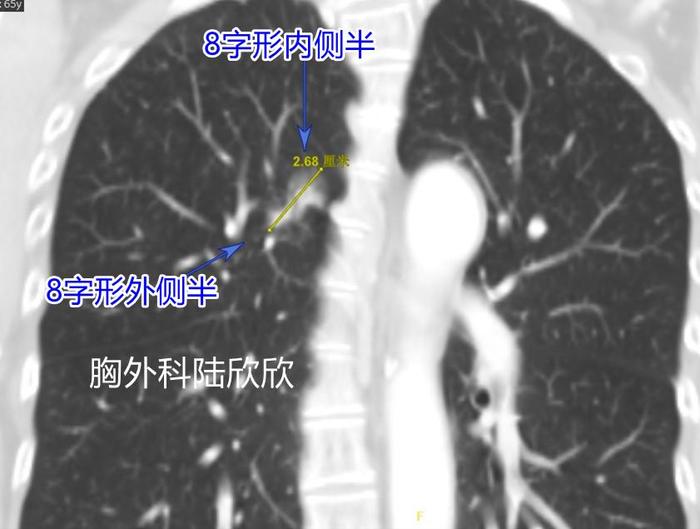

上图,为冠状位的CT第29层面,可见这个磨玻璃结节形状为8字形,内侧半和外侧半通过一个细桥相连。这张图显示结节的8字的形状最好。

上图,为冠状位的CT第28层面,可见这个磨玻璃结节形状为接近8字形,最大径是27毫米比横断面上的15毫米要大的多